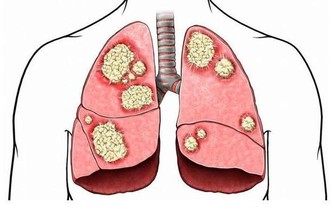

這些都是濕氣重的症狀,濕氣是人類健康的主要威脅。它雖然不是病,但是又比病更威脅。